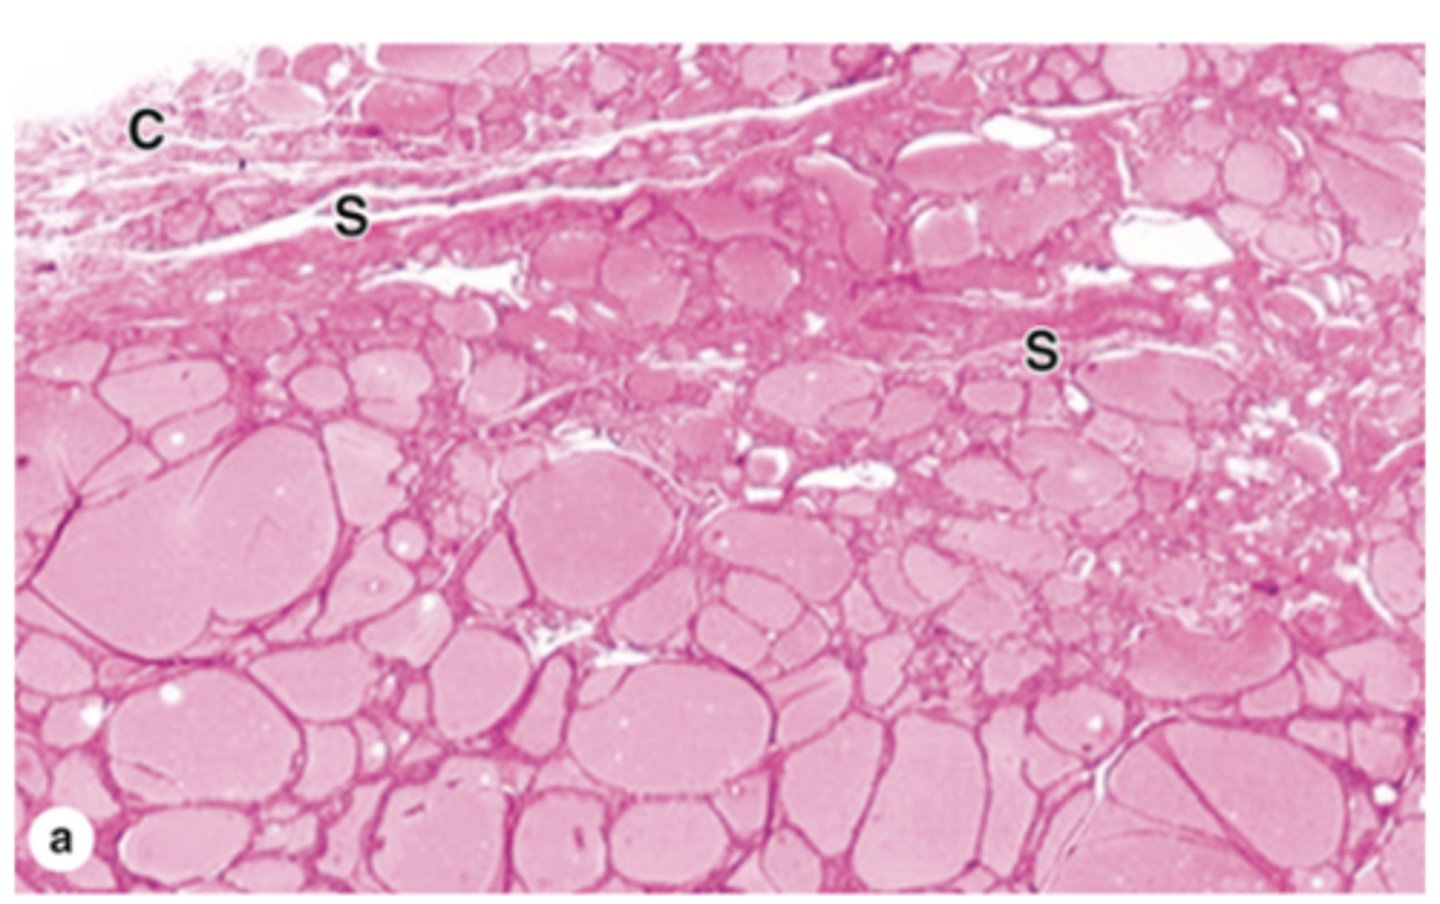

Where is the zona glomerulosa located, and what proportion of the adrenal cortex does it make up?

Just below the capsule, making up about 15% of the adrenal cortex.

What is the cellular arrangement and shape in the zona glomerulosa?

Closely packed, rounded or arched cords of columnar or pyramidal cells.

What hormones are secreted by the zona glomerulosa?

Mineralocorticoids, mainly aldosterone.

What type of blood supply is abundant in the zona glomerulosa?

Capillaries, part of the subcapsular arterial plexus.